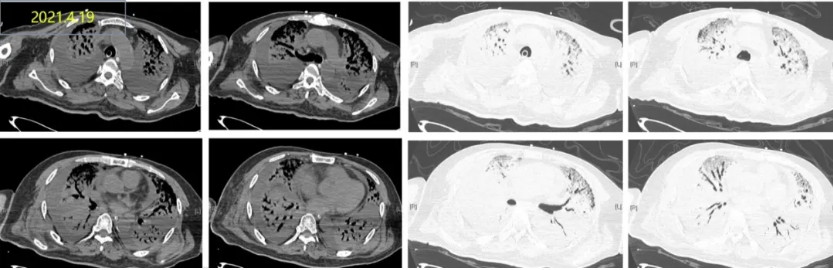

这是一名66岁男性患者的胸部CT对比,患者无明显诱因发热1月余,伴寒战,活动后呼吸困难加重,抗感染治疗效果不佳。

肺CT示双肺多发片状高密度影

5天前,氧合指数降至64.5mmHg,建VV-ECMO后收入RICU。